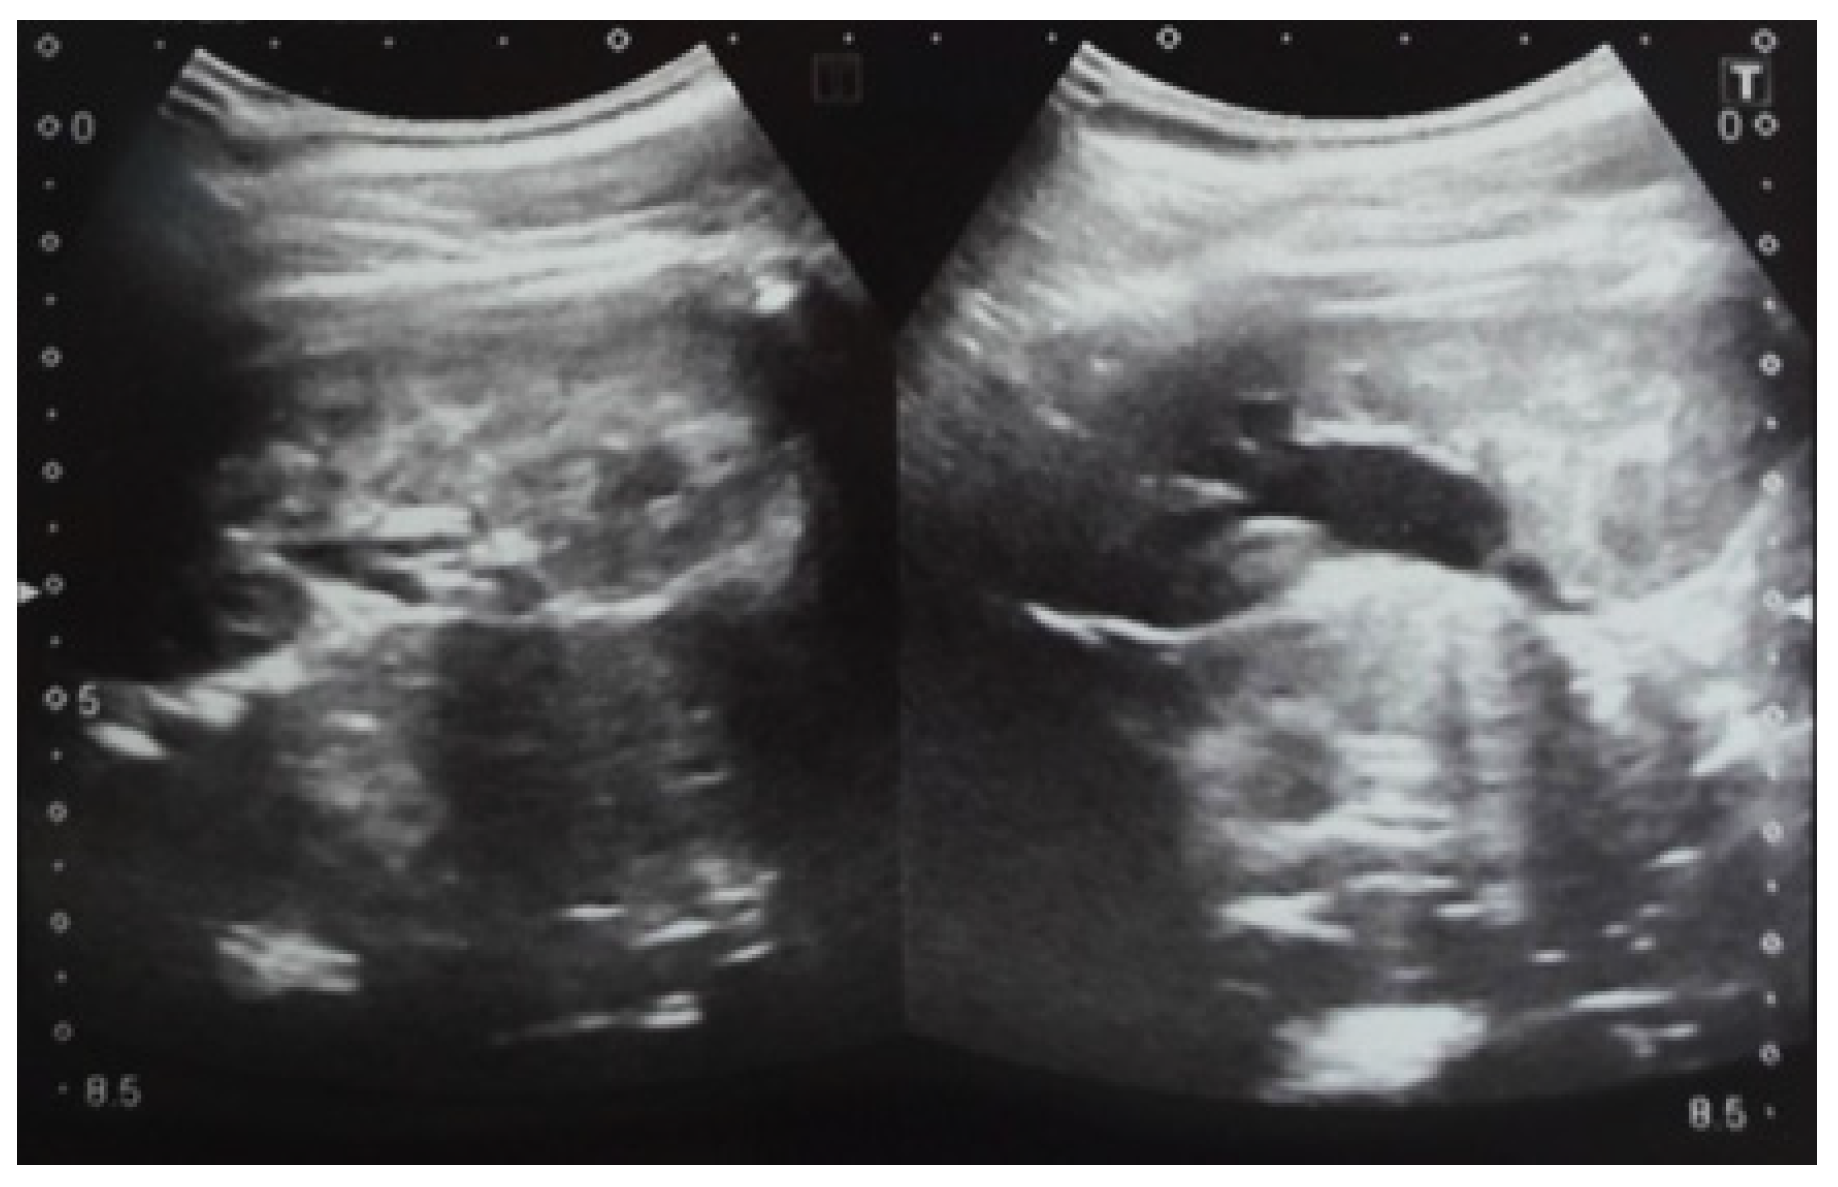

Our experience with congenital malformations of the urinary system refers to the following clinical case (Figure 2, Figure 3, Figure 4, Figure 5, Figure 6, Figure 7, Figure 8 and Figure 9). In the first case, during pregnancy, the 21-week ultrasound determined bilateral renal pyelectasia. The fetus had hydronephrosis on the right; at 31 weeks, it had bilateral hydrocalconephrosis; and at 32 weeks, bilateral pyelectasia. It suffered premature birth at 36 weeks, with complicated anomalies of the forces of contraction, prolonged birth, and birth weight of 2200 g. Postnatal ultrasonography was supplemented by intravenous urography, and bilateral hydronephrosis was determined. Hydrocalconephrosis on the left was discovered. The complete diagnosis was established: congenital renal malformation; bilateral pyelectasia; bilateral hydronephrosis; hydrocalconephrosis on the left; and severe reduced glomerular filtration rate (GFR), GFR > 2SD below mean.

Figure 4. Ultrasound at 31st week of gestation. Bilateral hydrocalconephrosis.

Figure 5. Ultrasound at 32 weeks of gestation. Bilateral pyelectasis.